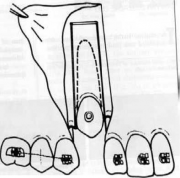

| 08:56, 19 ביוני 2013 | אנקילוטית3.png (קובץ) |  |

72 קילו־בייטים | Motyk | 1 | |